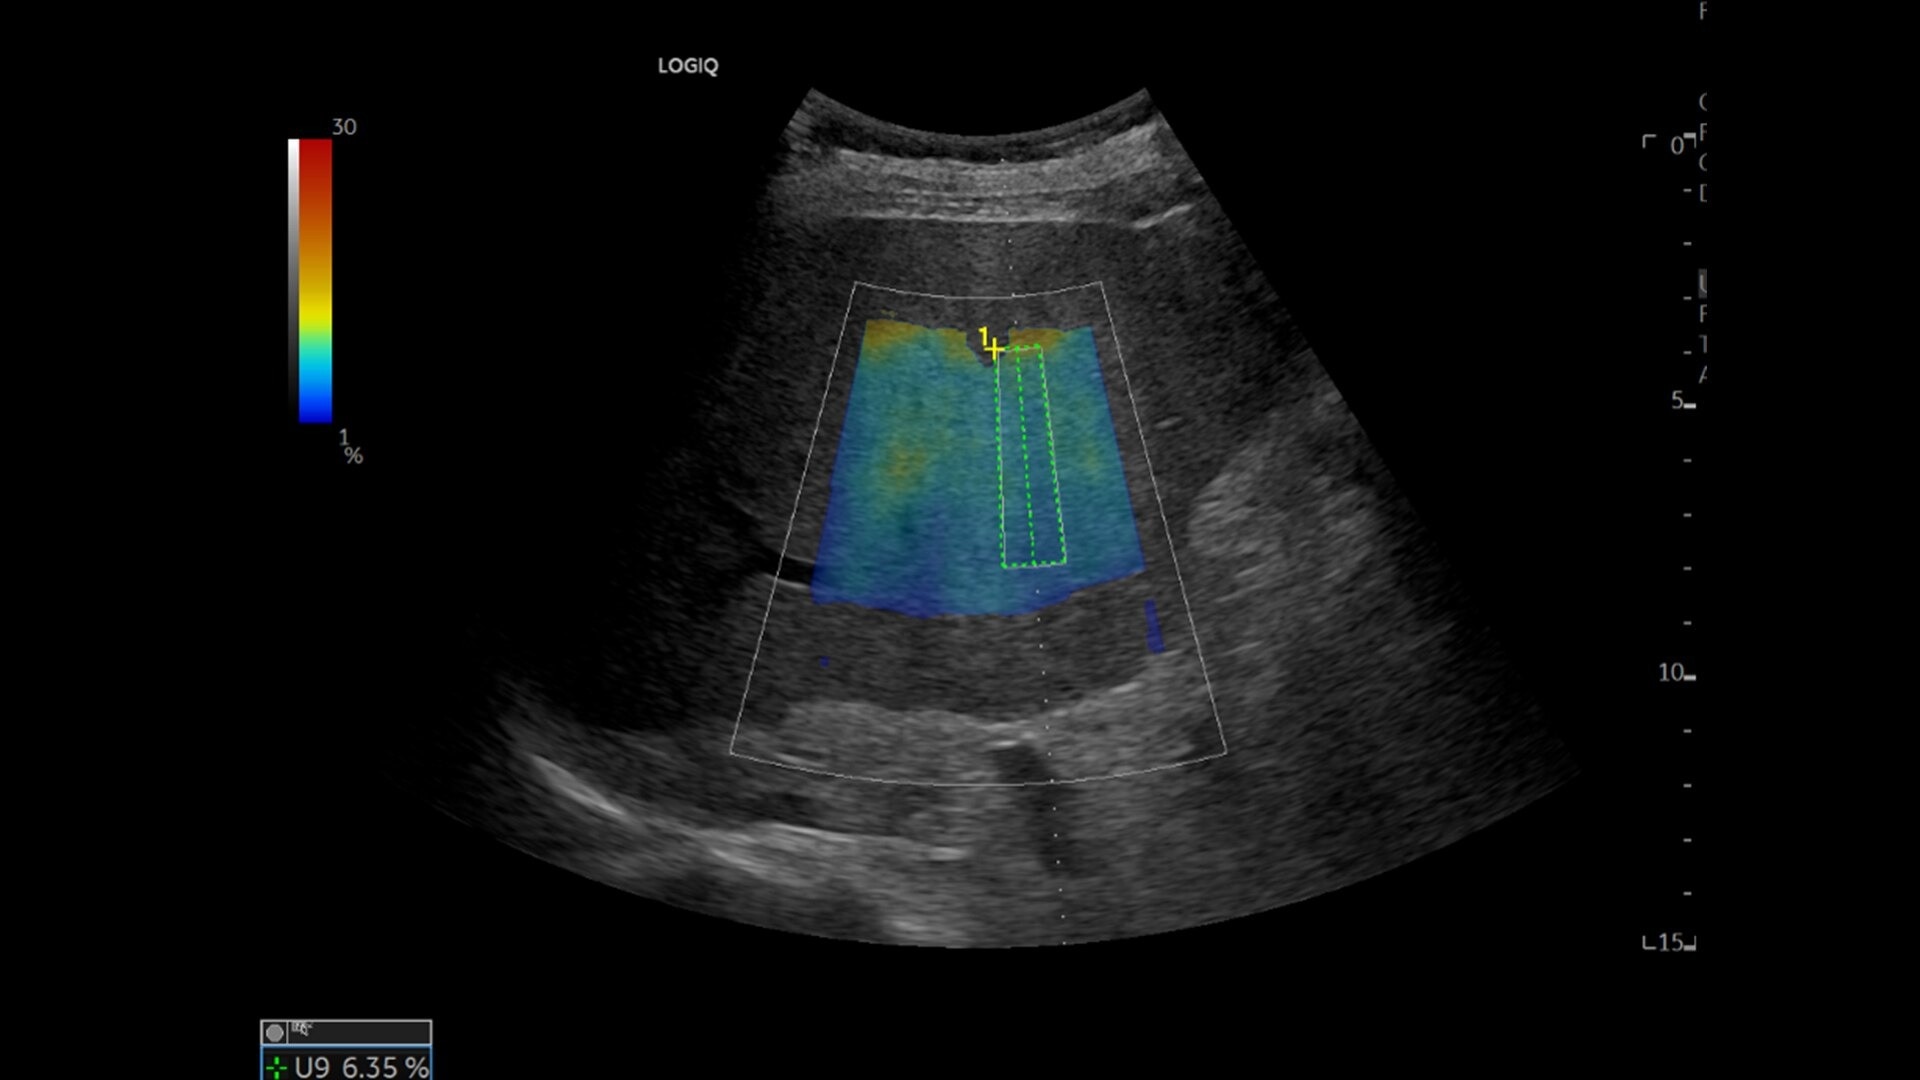

• Ultrasound-Guided Fat Fraction (UGFF) quantifies liver steatosis as a percentage, supporting detection and management - especially for patients with Metabolic Dysfunction-Associated Fatty Liver Disease (MAFLD)

• Hepatic Assistant: Combines 2D shear wave elastography and UGFF in a single workflow